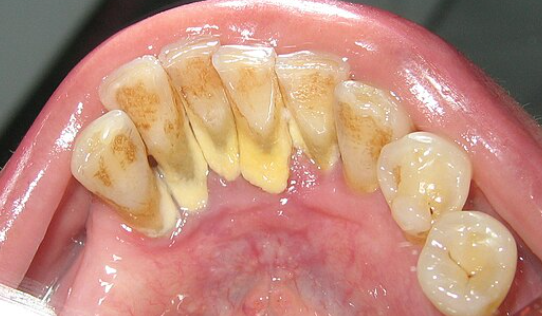

입 속에는 300여 종의 세균이 삽니다. 음식을 먹고 난 후 세균들은 침과 음식물에 섞여서 치아에 붙어 끈끈한 무색의 얇은 막을 만듭니다. 이처럼 세균들이 덩어리져 치아 면에 부착한 얇은 막을 치태라고 합니다.

치아를 제대로 닦지 않고 시간이 지나면 치태가 그대로 굳어져 딱딱한 돌 같은 치석이 됩니다. 치석의 표면에는 세균이 더 쉽게 부착하고 번식하여 잇몸 염증을 일으킵니다.

플라크(plaque)와 치석이 쌓여 잇몸이 치아로부터 떨어지게 되며, 이 틈이 벌어지면서 치주낭이 형성됩니다.

잇몸병(치주질환)은 주로 30대 중반부터 시작됩니다. 구강 위생 관리를 소홀히 하면 치석이 쌓이고, 염증이 생기면서 치아 주위 잇몸과 치조골이 손상됩니다.